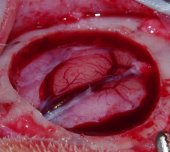

– Goyenvalle, 2012 (2) – Source : Rapport CORTECS – Rapport sur l’ostéopathie crânienne établi par le Collectif d’enseignement et de recherche en esprit critique et sciences (CORTECS), p.76-77 – Il s’agit d’un mémoire d’un étudiant en école vétérinaire – Si je me présente page 6 comme – un « jeune » étudiant en ostéopathie – trois paragraphes plus tard je précise que je suis Enseignant Chercheur en Chirurgie à ONIRIS, membre d’une équipe INSERM. – Il n’y a pas mention d’objectifs de recherche clairement défini ni de formulation d’hypothèses de recherche a priori. Ce qui s’apparente le plus à une présentation d’objectifs de recherche dans ce mémoire est ce passage, page 6: « Me voilà en tout cas, à cette date du 7 Mai 2009, avec une certitude : il existe bien un mouvement rythmique du cerveau; mais aussi beaucoup de questions qui persistent : – pourquoi autant d’aléa dans le délai d’apparition de ce mouvement après ouverture de la boite crânienne ? – pourquoi une telle impression de variabilité de ce mouvement entre différents animaux, tant sur le plan de la fréquence que de l’amplitude ? – Cette motilité cérébrale, est-elle synchrone d’autres mouvements physiologiques comme la respiration ou la fonction cardiaque ? – existe-t-il une relation entre la contraction/expansion cérébrale et les mouvements de flexion/extension du sacrum, comme le laisse penser le concept cranio-sacré de Sutherland ? » – En quoi cela ne correspond pas à des objectifs de recherche ? Je pose 4 questions auxquelles je vais essayer de répondre – Ce travail part donc du présupposé qu’il existe bel et bien un « mouvement rythmique du cerveau », sans pour autant renvoyer à une littérature spécifique – C’est une observation que j’ai faite de mes yeux et filmée avec un caméscope de marque SONY etc…, à l’occasion d’une intervention chirurgicale pratiquée le 7 Mai 2009, comme je le rapporte au 3ème paragraphe de la page 6, en donnant la référence internet montrant la vidéo : http://www.osteo4pattes.fr/films/vetosteo2wmv.mpg). Une méthodologie détaillée est ensuite présentée. Nous allons la présenter puis voir si elle permet de répondre aux potentiels objectifs de recherche formulés. – Sept lapines de race New Zealand, provenant d’un élevage, ont été anesthésiées, puis craniotomisées. Avant et après craniotomie, certains paramètres ont été mesurés durant 45 minutes sur chacune des lapines. Le protocole de relevé des mesures n’a pas été défini a priori ni standardisé. – Sur quelle base les auteurs peuvent dire que les paramètres de mesures n’ont pas été définis à priori, bien au contraire. Je précise p.7 « En tant qu’enseignant – chercheur en Chirurgie, j’ai la chance d’avoir accès à des infrastructures et moyens qui me permettent de réitérer les observations faites précédemment, et donc d’élaborer un protocole d’étude pour apporter des réponses à mes différentes interrogations concernant la pulsatilité cérébrale…. » J’ai donc rédigé mon protocole et ensuite réalisé l’étude, comme cela doit se faire pour toute étude. – Les paramètres mesurés ont été : la fréquence cardiaque, la fréquence respiratoire, la fréquence thoracique, la pulsatilité cérébrale (à travers sa fréquence (3) et son amplitude(4), la fréquence du cycle Inspir/Expir du sacrum (5), les restrictions de mobilité du sacrum(6). Nous avons ajouté une description de ces derniers paramètres en note de bas de page car ils sont spécifiques aux ostéopathes. Deux nouveaux éléments posent problème à ce stade : l’existence physique des paramètres étudiés ; la validité et la fiabilité des techniques utilisées pour les mesurer (Notre partie XXX porte d’ailleurs sur l’étude de la fiabilité des outils et techniques diagnostics ostéopathiques). Il n’est à a aucun moment mention de la façon dont la mesure de ces paramètres va permettre de répondre aux nombreuses questions de recherches soulevées initialement. – A noter que les deux paramètres qui posent problème de validité aux auteurs ne sont utiles que pour répondre à la 4ème et dernière question de la liste des objectifs rapportés précédemment. Pour les trois premières questions, les méthodes d’évaluation des paramètres mesurés ne peuvent pas être remises en question… Elles font d’ailleurs l’objet d’une analyse critique de la méthodologie dans la première partie de la discussion. Je rappelle juste à ce stade, que la partie Matériel et Méthodes est là pour décrire précisément la méthodologie utilisée. A l’exception des paramètres (5) et (6) uniquement accessibles aux ostéopathes, tout à chacun peut, sur la base du Matériel et Méthodes rapporté, reproduire l’étude à l’identique et ainsi faire ses propres observations. – La partie résultats du mémoire s’articule en deux temps : une synthèse par individu des paramètres observés ; une synthèse par paramètre. Cette partie ne permet en rien de répondre aux questions de recherches précédemment formulées. – Comme dans toute étude scientifique, la partie Résultat expose les résultats bruts sans aucune analyse. Cela rend la lecture de la partie Résultats fastidieuse, mais c’est ainsi selon les bonnes pratiques de rédaction scientifique. L’analyse des résultats est faite dans la partie Discussion. La partie discussion est constituée principalement (pp.37 à 49) de sous-parties intitulées respectivement. En toute objectivité, il conviendrait de préciser que le Matériel et Méthode fait l’objet d’une analyse critique (page32 à 35) : – la dure-mère : élément de tenségrité de l’axe cranio-sacré ; – la pulsatilité cérébrale existe ; – la pulsatilité cérébrale : un rythme propre ? – la pulsatilité cérébrale : moteur du MRP ? Dans ces sous-parties, il n’est à aucun moment fait mention des expériences menées précédemment. – Le terme « à aucun moment » révèle une lecture très incomplète du document. Pour exemple : * dans le paragraphe « Dure-mère : élément de tenségrité de l’axe cranio-sacré » , est écrit dans le 3ème paragraphe de la page 38 « Dans notre étude, à la suite de la craniotomie, le système de tenségrité de l’axe cranio-sacré s’est retrouvé modifié, en particulier la dure-mère (par son effraction), et par voie de conséquence le LCR (fuite de LCR à l’origine d’une baisse de volume et de pression) ….Lors d’effraction latéralisée, nous avons ressenti, en plus de la flexion, l’apparition d’une rotation du sacrum, avec une rotation toujours dans le même sens par rapport au côté de l’effraction. Ce qui fait que la main sur le sacrum, je pouvais annoncer au chirurgien de quel côté se produit l’effraction dure-mérienne. » – dans le paragraphe « la pulsatilité cérébrale existe», est écrit dans le 3ème paragraphe de la page 41 « Ces différentes observations rapportées dans l’ouvrage de Swedenborg concordent parfaitement avec les nôtres. A deux différences près : (1) – qu’il n’est jamais rapporté l’existence d’un délai dans l’apparition de la pulsatilité cérébrale par rapport au moment de la craniotomie. Il faut noter que toutes les observations rapportées à l’époque proviennent de patients (humains ou animaux) parfaitement vigiles – avec toute l’horreur que cela représente. Cela ne fait que renforcer notre conviction (émise précédemment) que l’anesthésique utilisé dans notre étude est à l’origine de l’apparition retardée de la pulsatilité cérébrale par rapport au moment de la craniotomie. (2)- Nos observations montrent que l’effraction dure-mérienne large est une condition nécessaire à l’observation visuelle d’un mouvement d’expansion / rétraction du tissu cérébral. Aucune pulsatilité cérébrale n’a été observé pour les lapins n°2 et 3, animaux pour lesquels l’intégrité de la dure-mère a été largement préservée. Pour tous les autres lapins (n°1, n°4, n°5, n°6 et n°7), dès lors que la brèche dure-mérienne est large, un mouvement d’expansion / rétraction du tissu cérébral apparaît après un certain laps de temps (en moyenne 45-50 minutes postinduction anesthésique). Seul Ridley précise dans son observation que la dure-mère a été ouverte. Pour les autres, rien n’est précisé….. Et ainsi de suite dans les différents paragraphes de la discussion des résultats. Je laisse le soin aux lecteurs de se faire sa propre opinion. – L’auteur cite des travaux ou hypothèses d’autres auteurs. Un tableau présenté dans son étude résume les résultats des expériences menées sur les lapines sans faire mention du MRP. – Cela montre que les membres du groupe CORTECS n’ont pas bien lu les objectifs de mon étude, qui n’ont rien à voir avec le MRP. – Cette étude ne nous apporte aucune preuve d’existence du MRP – Contrairement à ce que sous-entendent les rapporteurs du CORTECS, l’objectif de cette étude, comme le titre l’indique, n’est pas de prouver l’existence du MRP, mais d’en savoir un peu plus sur le rôle de la pulsatilité cérébrale dans le concept cranio-sacré tel que décrit par Sutherland. – elle pose au départ que ce phénomène existe – Il y a là de la part des auteurs du groupe CORTECS clairement confusion entre le MRP et pulsatilité cérébrale. Je pose au départ que la pulsatilité cérébrale existe, car j’ai personnellement observé ce phénomène, je l’ai d’ailleurs filmé. D’ailleurs tous les neurochirurgiens l’observent au quotidien, et qu’elle se contentera d’étudier certaines de ses caractéristiques. – La méthodologie déployée ne permet pas de répondre clairement aux questions de recherche formulées – Comment peut on oser dire que le comptage visuel des mouvements cérébraux n’est pas fiable ? Comment oser dire que le comptage visuel des mouvements thoraciques couplé à un comptage par un capnomètre n’est pas fiable pour mesurer la fréquence des mouvements respiratoires ? Comment peut-on oser dire que l’utilisation d’un ECG n’est pas fiable pour mesurer la fréquence cardiaque ? – Qui ne sont pas reprises dans la partie résultat ou discussion – Comment peut-on oser dire que les questions ne sont pas reprises dans la discussion, eu égard à mes remarques précédentes? – Les principales limites de cette étude sont : – l’absence de présentation claire des objectifs visés par l’étude, et l’absence d’identification des critères de jugements permettant de répondre aux questions de recherche imprécises ; – la validité et la fiabilité des outils utilisés pour mesurer les paramètres ; – l’existence physique de certains des paramètres étudiée : existent-ils réellement ? – Dans son concept cranio-sacré, Sutherland considérait la mobilité inhérente du cerveau (que j’ai appelé la pulsatilité cérébrale) comme le moteur du MRP. L’une des conclusions de mon étude (dernier paragraphe p.48) est que « … à la question posée « Pulsatilité cérébrale : moteur du MRP ? », ma réponse actuelle serait non… ». Ma conclusion remet donc en question le concept cranio-sacré, telle que décrit par Sutherland. Cela peut paraître surprenant de la part d’un vétérinaire ostéopathe, mais l’honnêteté scientifique conduit parfois à remettre en cause certaines idées. Loin de moi l’idée de vouloir prouver que le MRP existe sur la base de résultats sans valeurs scientifiques, comme le laisse sous-entendre les auteurs du Cortecs. Mais peut-être que les auteurs du CORTECS font une allergie systématique à tout document parlant du MRP….. Je laisse maintenant le soin aux lecteurs de se faire sa propre opinion sur mon étude et sur l’analyse qui en a été faite par le Cortecs. Notes 2 Goyenvalle E., La pulsatilité cérébrale dans le concept cranio-sacré – Étude chez le Lapin, Mémoire en vue de l’obtention du diplôme d’ostéopathie vétérinaire d’ON×Î×S – École Nationale Vétérinaire de Nantes 2012, revue ostéo4pattes. https://revue.osteo4pattes.fr/IMG/pdf/Memoire_Osteopathie_26-06-12_goyenvalle.pdf 3 « À travers l’ouverture de la boite crânienne, le cerveau a montré des mouvements rythmiques d’expansion/contraction, se traduisant par une montée / descente de la surface cérébrale par rapport à la marge osseuse du défaut osseux de craniotomie. La fréquence de ces cycles montée/descente a été comptabilisée par minute. ». Ibid. 4 «Elle a été classée en trois groupes : faible (mouvement limite perceptible), moyenne (mouvement perceptible sans dépasser les limites des marges de craniotomie), élevée (mouvement perceptible qui dépasse les marges de la craniotomie) ». Ibid. 5 « La main gauche est posée sur le sacrum à l’écoute du mouvement d’inspir/expir (Extension/Flexion) de ce dernier. La fréquence des cycles Inspir / Expir a été comptabilisée par minute ». Ibid. 6 « La main posée sur le sacrum évalue les restrictions de mobilité pouvant être observée (flexion, extension, rotation, side-bending) ». Ibid.NDLR : Ces quelques lignes montrent que quelles que soient la motivation et la bonne volonté des auteurs de ce rapport, de nombreuses imprécisions ou incompréhensions ou élusions ont été commises. Quoi de plus normal quand on passe en revue des dizaines d’études et c’est bien là la limite de l’exercice qu’ils ont accompli, et qui montrent que d’études en études le petit parti pris plus ou moins conscient du départ s’installe et donne une conclusion sinon partiale en tous cas qui ne trie pas correctement le bon grain de l’ivraie … Effectivement Eric nous a très bien parlé de pulsatilité cérébrale observée sous plusieurs angles … ce n’est pas un présupposé de sa part, comme affirmé par les auteurs du Cortecs, c’est une observation … qualificatif assez péjoratif quand infondé quand on commence l’étude d’une étude et qui laisse penser que sa propre étude est entachée de présupposés. L’arroseur arrosé ! Autre malentendu rapporté ces lapins n’ont pas été sacrifiés sur l’autel de la probation le la pulsatilité cérébrale mais cette expérimentation s’appuyait sur la première expérience pour laquelle ces lapins étaient opérés : la biocompatibilité de matériaux pour restaurer une boite crânienne abimée (par un accident de la route ou un éclat d’obus …). Aucune souffrance supplémentaire n’a été infligée pour les besoins de cette deuxième expérience pendant l’expérience. J’aimerais actualiser ma petite touche personnelle car ce sujet, bien que datant maintenant d’une dizaine d’année est brûlant d’actualités. Des experts (autoproclamés il faut le dire) prennent un sujet, regarde les études réalisées sur le sujet et concluent sur la validité scientifique de ce qui a été produit. Cela s’appelle une méta étude et c’est en ce moment le nec plus ultra de la science. Mais comme pour tout, le diable se niche dans les détails. Et sur cette étude particulière, ils sont pris en flagrant délit de lecture en diagonale et de parti pris. Qu’en est ‘il alors pour les autres études du rapport ? Et l’on voudrait que ces gens-là nous expliquent « ce qui est » et doit être à l’exclusion de tout autre ? Vous trouverez dans ces articles sur les cadres de pensée entre autres comment une telle méta étude a « démontré » avec gracieuse mauvaise foi que l’homéopathie ne valait rien : http://osteo4pattes-sdo.eu/spip.php?article2959. Or, ici, Eric nous montre (pour nos yeux) que la pulsatilité du cerveau existe et est quelque chose d’incontournable. De plus, Eric nous dit aussi qu’il ne sait pas après son étude si le MRP et la pulsatilité observées sont liés. Vous savez sans doute que je pense que pour expliquer ce que nous sentons dans nos mains il faut passer par la résonance d’un système de tenségrité. Ai-je tort ou raison scientifiquement ? Je n’en sais rien. Mais je sais deux choses : 1) C’est que l’explication de Sutherland n’est peut-être pas la bonne, tant elle piétine à fournir des preuves de son existence. 2) Je sais aussi que nous sentons vraiment quelque chose dans nos mains que nous nommons MRP et que ce concept produit des effets. Alors, Il faudra bien effectivement un jour que science et expérience se rejoignent. Mais je suis aussi persuadé que pour cela il faudra que la science médicale élargisse sa conception de la vie …